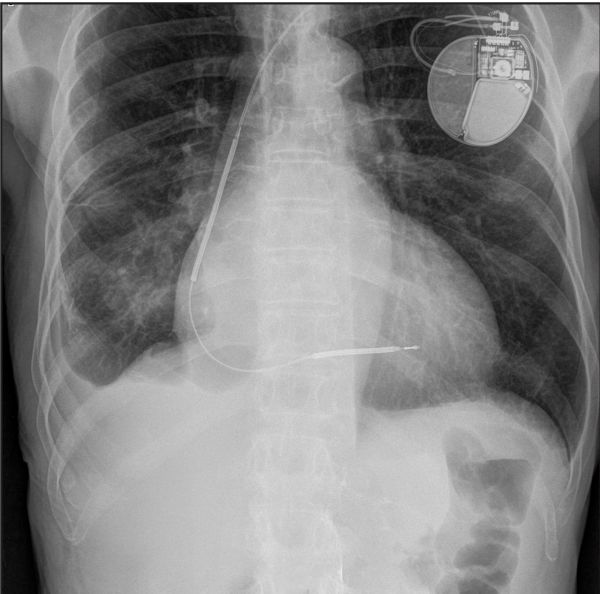

RadiologicTechnologists are medical personnel who perform diagnostic imaging exams and administer radiation therapy treatments. Many technologists have cross trained and specialize in specific imaging techniques. Prairie Lakes relationship with Consulting Radiologists Ltd. (CRL) has provided the opportunity to expand on the type of imaging exams available in Watertown. Prairie Lakes RadiologicTechnologists work with Radiologists at CRL to provide services like breast imaging, nuclear medicine, and musculosketal imaging.